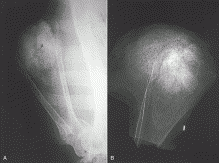

Tumors of the Skeletal System » Photos